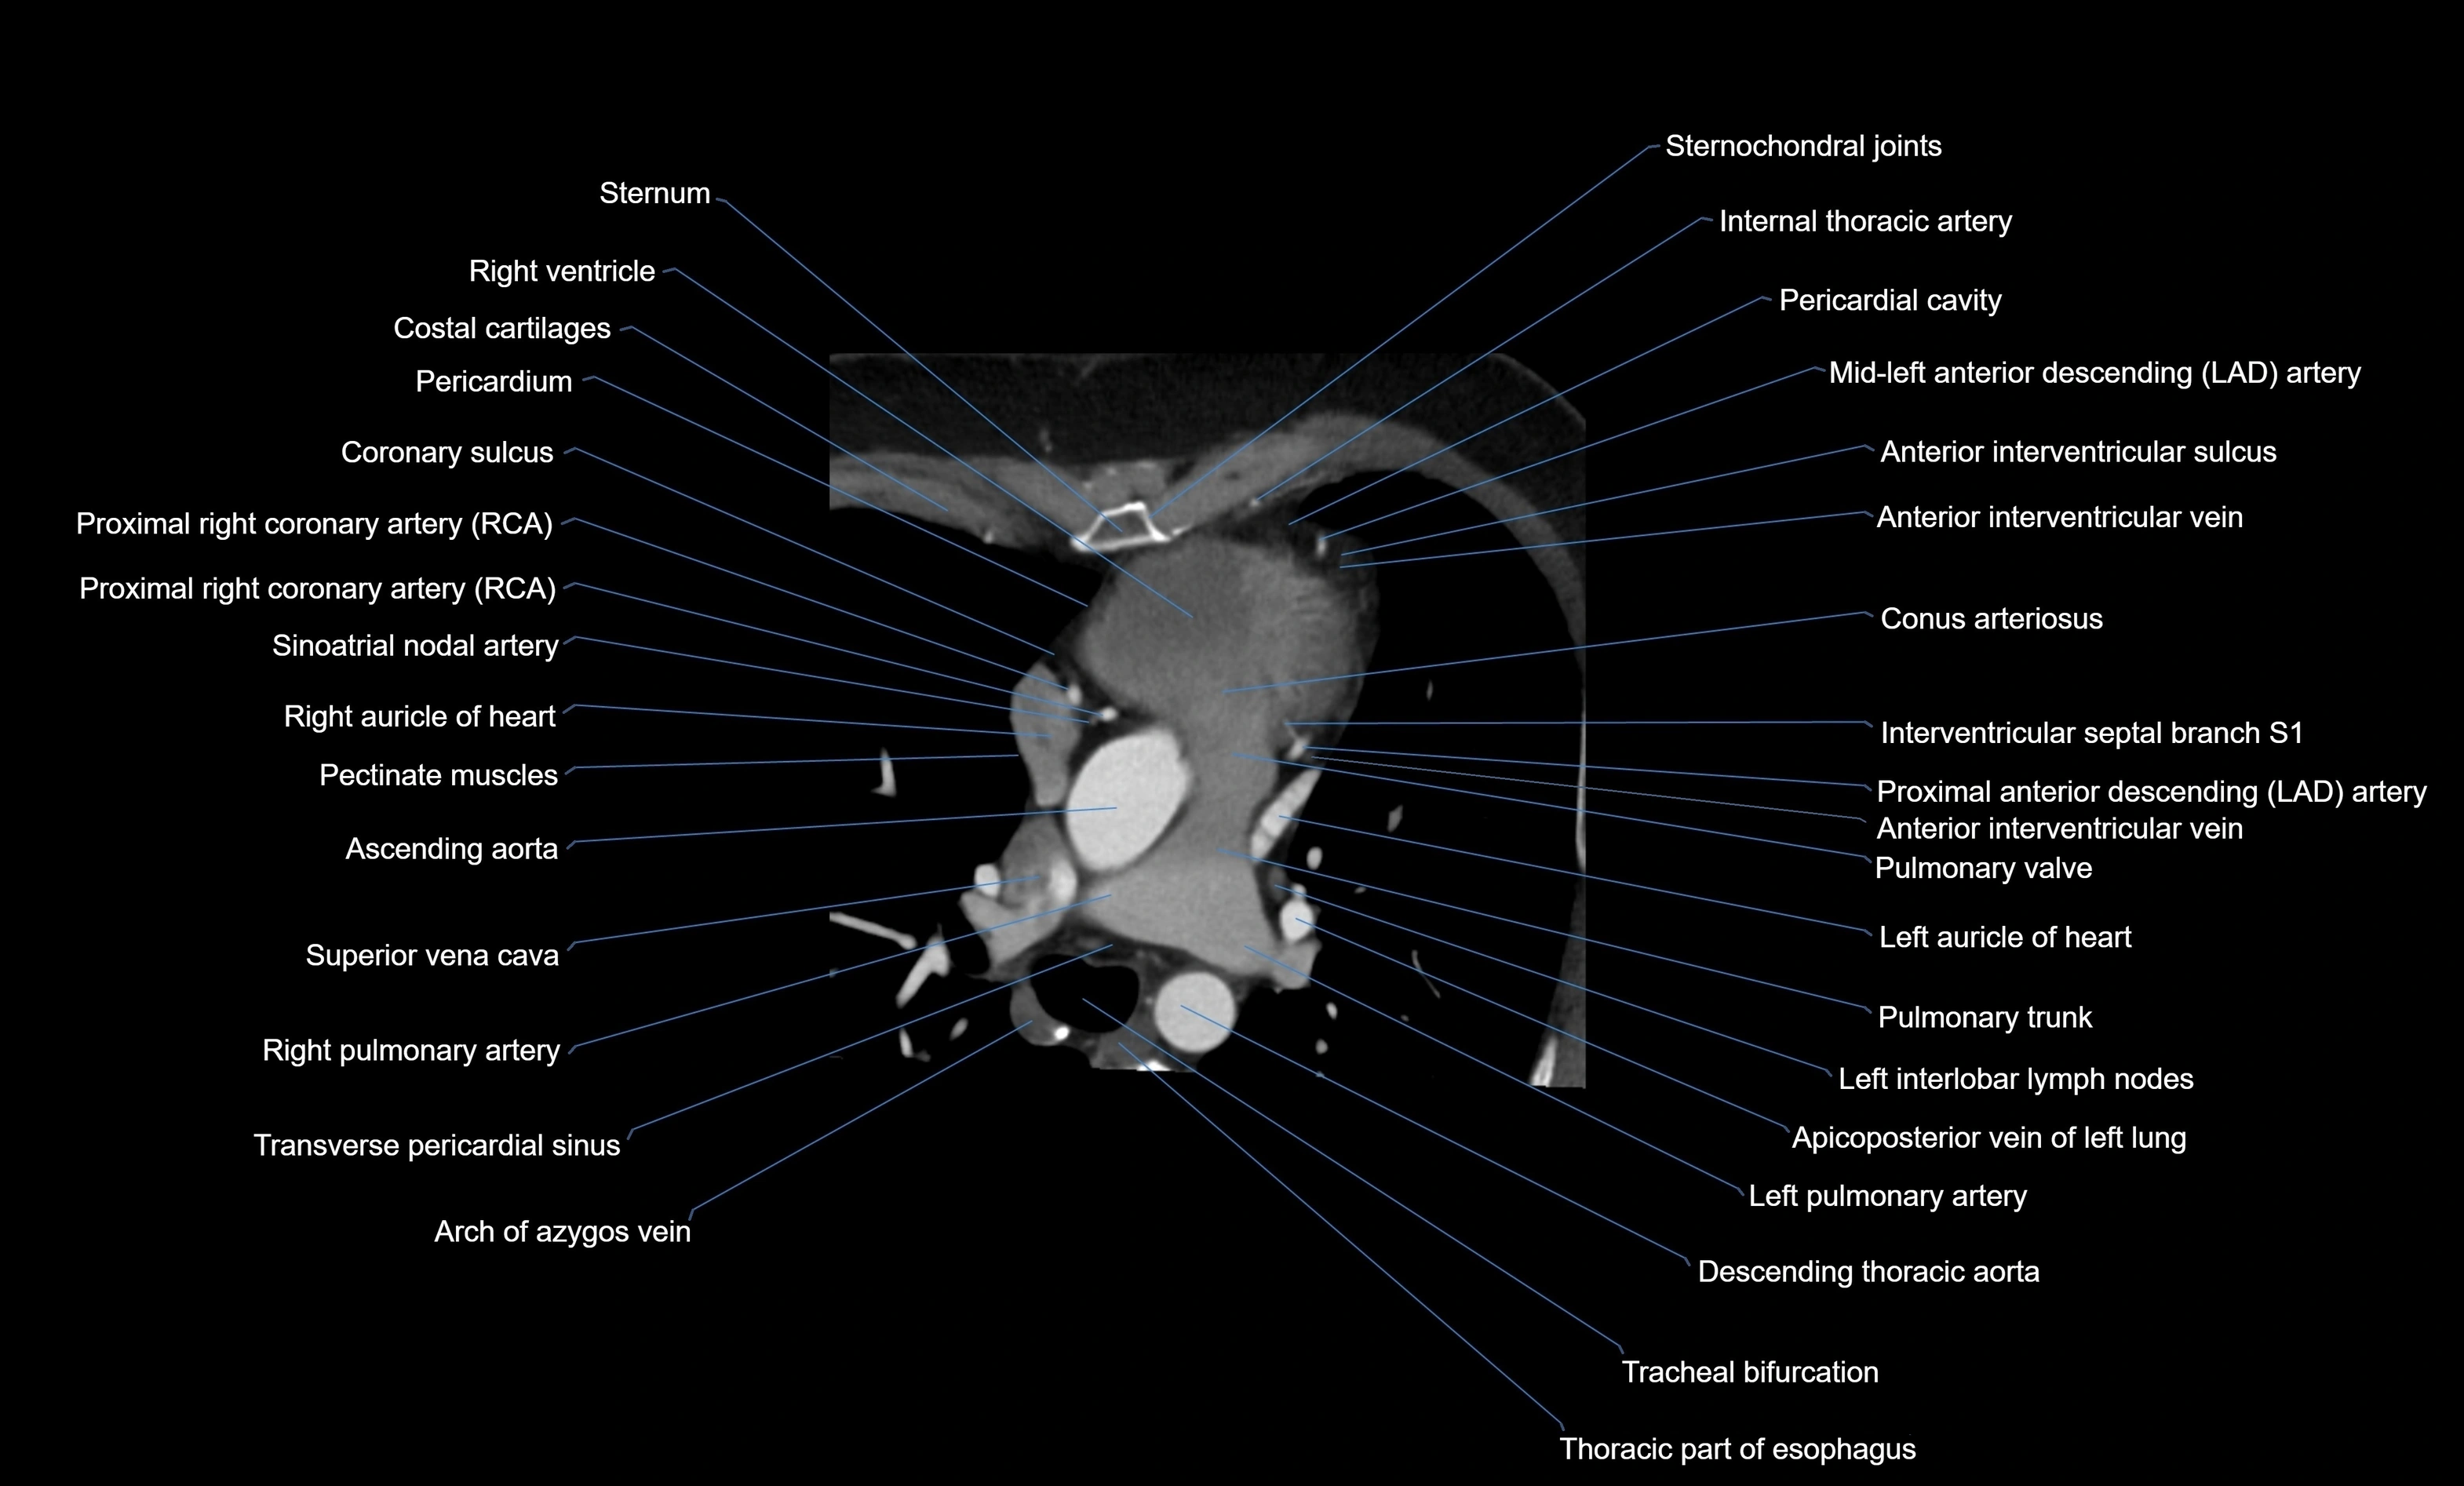

CT images